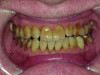

Close-up view of patient’s dentition in 2009.

Figure 1